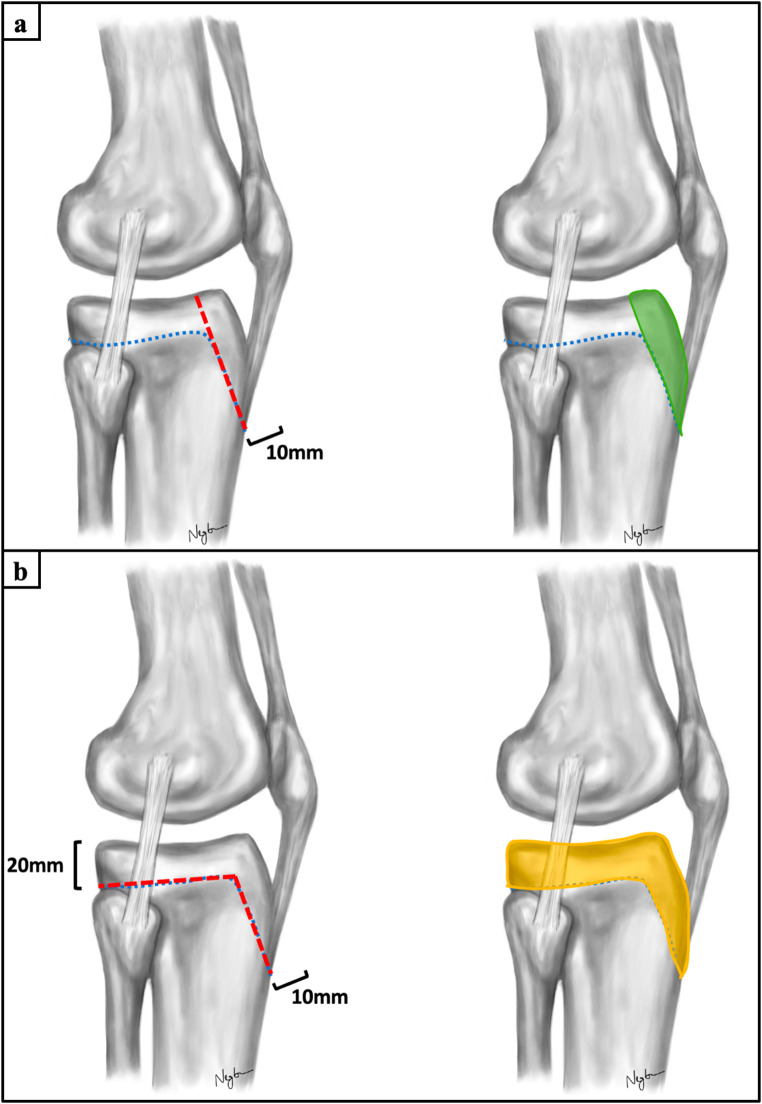

Methods: Two different types of apoepiphyseal tibial tubercle avulsion fractures were created in 40 proximal tibiae according to the modified Ogden classification: (1) Ogden type IIIA and (2) Ogden type IV. The fractures were fixed with either isolated apophyseal screws or additionally with a medial plate or epiphyseal screws. All specimens were biomechanically tested under progressively increasing cyclic loading until failure, while capturing the interfragmentary movements with motion tracking.